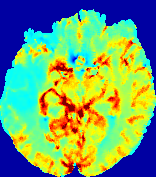

4.3.2 Diffusion Imaging via Advection-Diffusion

Slice #1Slice #2Slice #3Slice #4Slice #5Slice #6Dgtsuperscript𝐷gtD^{\text{gt}}Refer to captionRefer to captionRefer to captionRefer to captionRefer to captionRefer to captionDestsuperscript𝐷estD^{\text{est}}Refer to captionRefer to captionRefer to captionRefer to captionRefer to captionRefer to captionRefer to caption0.300.300.300.240.240.240.180.180.180.120.120.120.060.060.060.000.000.00(mm2/s)𝑚superscript𝑚2𝑠(mm^{2}/s)𝐕est𝟐subscriptnormsuperscript𝐕est2\|\bf{V}^{\text{est}}\|_{2}Refer to captionRefer to captionRefer to captionRefer to captionRefer to captionRefer to captionRefer to caption0.00300.00300.00300.00240.00240.00240.00180.00180.00180.00120.00120.00120.00060.00060.00060.00000.00000.0000(mm/s)𝑚𝑚𝑠(mm/s)

Figure 15: PIANO identifiability testing: diffusion imaging via advection-diffusion. Top row shows Dgtsuperscript𝐷gtD^{\text{gt}} used for simulating ground truth pure diffusion. Rows below show the estimated Destsuperscript𝐷estD^{\text{est}} and 𝐕est2subscriptnormsuperscript𝐕est2\|{\bf{V}}^{\text{est}}\|_{2} on corresponding slices. Note that the plotted value scale for 𝐕est2subscriptnormsuperscript𝐕est2\|{\bf{V}}^{\text{est}}\|_{2} is 0.01 of that for Dgtsuperscript𝐷gtD^{\text{gt}} and Destsuperscript𝐷estD^{\text{est}}.

Similarly, we test the behavior of PIANO when estimating both advection and diffusion from a pure diffusion-driven process. The goal is to determine if PIANO is able to recognize that there is only diffusion governing the given concentration time-series. We use the same ‘Diffusion Imaging’ data simulation of Sec. 4.2.1 as the concentration dataset, PIANO estimates both velocity 𝐕estsuperscript𝐕est{\bf{V}}^{\text{est}} and diffusivity Destsuperscript𝐷estD^{\text{est}}. Estimation results in Fig. 15 confirm PIANO’s identifiability again: the estimated 𝐕est2subscriptnormsuperscript𝐕est2\|{\bf{V}}^{\text{est}}\|_{2} is almost invisible compared to Destsuperscript𝐷estD^{\text{est}}, even plotted with a 1%percent11\% value range compared to that for Destsuperscript𝐷estD^{\text{est}}. On the other hand, Destsuperscript𝐷estD^{\text{est}} achieves comparable estimation performance as ‘Diffusion Imaging via Diffusion’ in which PIANO predicts Destsuperscript𝐷estD^{\text{est}} alone (shown in Fig. 13).